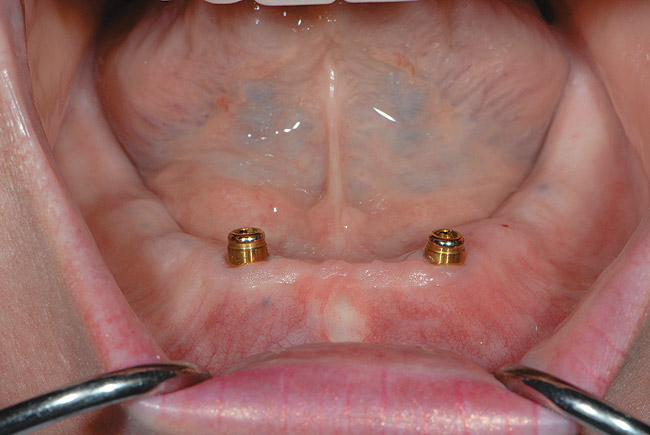

When dental implants were introduced by Brånemark, they were intended primarily for the completely edentulous patient, specifically the edentulous mandible. The initial prosthesis was a fixed restoration commonly referred to as a fixed bone anchored bridge. That particular prosthetic design is now the fixed-detachable hybrid prosthesis and has been highly successful for both the implants and prostheses.12,13 Implants have also been used for overdenture restorations14 and can be implant-assisted or implant-supported. With implant-assisted prostheses, the implants and mucoperiosteum share the forces of occlusion. A simple two-implant overdenture, either a Hader Bar® (Sterngold™, Attleboro, MA) or Locator® abutment (Zest Anchors, Escondido, CA), are examples of implant-assisted overlay prostheses and are always a removable restoration (Figure 4 and Figure 5). With implant-supported prostheses, the forces of occlusion are borne solely by the implants. This prosthesis can be an overlay prosthesis or a fixed restoration. Milled bar restorations, overdentures with bar substructures, and metal ceramic restorations attached to implant abutments by either screws or cement are examples of implant-supported restorations. One of the primary benefits of using dental implants in edentulous patients is the preservation of the residual bone, which will provide a better opportunity for future successful prosthetic restorations.

Figure 5  Locator abutments placed on implants can also be used for an implant-assisted prosthesis.

Figure 5